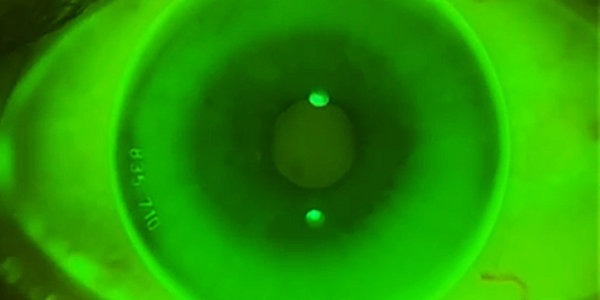

TIEDRA présente ALEXA AR®, Orthokératologie de haute résolution

TIEDRA annonce le lancement sur le marché français d'un nouveau concept en Orthokératologie de haute résolution avec sa lentille ALEXA AR.